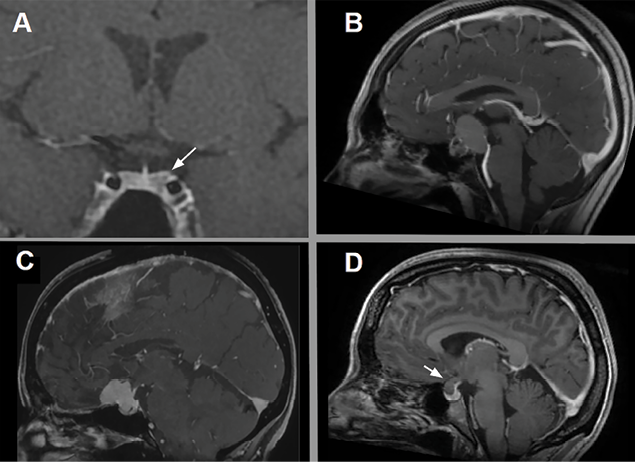

Figura 1. Lesiones selares más frecuentes. A: Adenoma hipofisario. B: Craneofaringioma. C: Meningioma del tuberculum selar. D: Quiste de la bolsa de Rathke